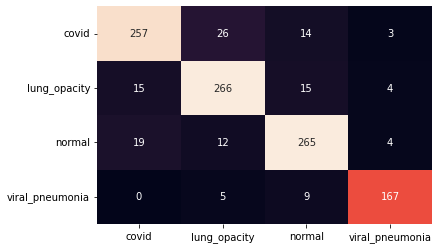

III.2 Classification results

The training procedure in all scenarios has converged. Looking at the evolution of training and validation accuracy (Fig. 11a) indicates that a larger validation dataset would be beneficial. To stabilise the classifier training a procedure of multiple training runs to select the best model is used (Materials and methods). Resulting classifiers are able to discriminate between classes with good precision, for example, see the confusion matrix of the best overall model presented in Fig. 11b. It can also be seen that for the normal class, the rate of misclassified images as COVID-19 ones is higher than for other classes. This effect is present for all models although smaller for the ones based on the EfficientNet-B0 architecture. In addition, the EfficientNet-B0 variants excel if the correct classification of viral pneumonia class images with the smallest rate of errors. However, the EfficientNet-B0 GAN augmentation scenario shows increased misclassification of healthy images which leads to a poor performance. The evolution of the training accuracy as well as confusion matrices for all models are summarised at the end of this section.

Training results for the two architectures are summarised in Figs. 13, 14, 15, 16, and Table 3. For each architecture four scenarios are considered as described in Training process part of the Materials and methods Section.